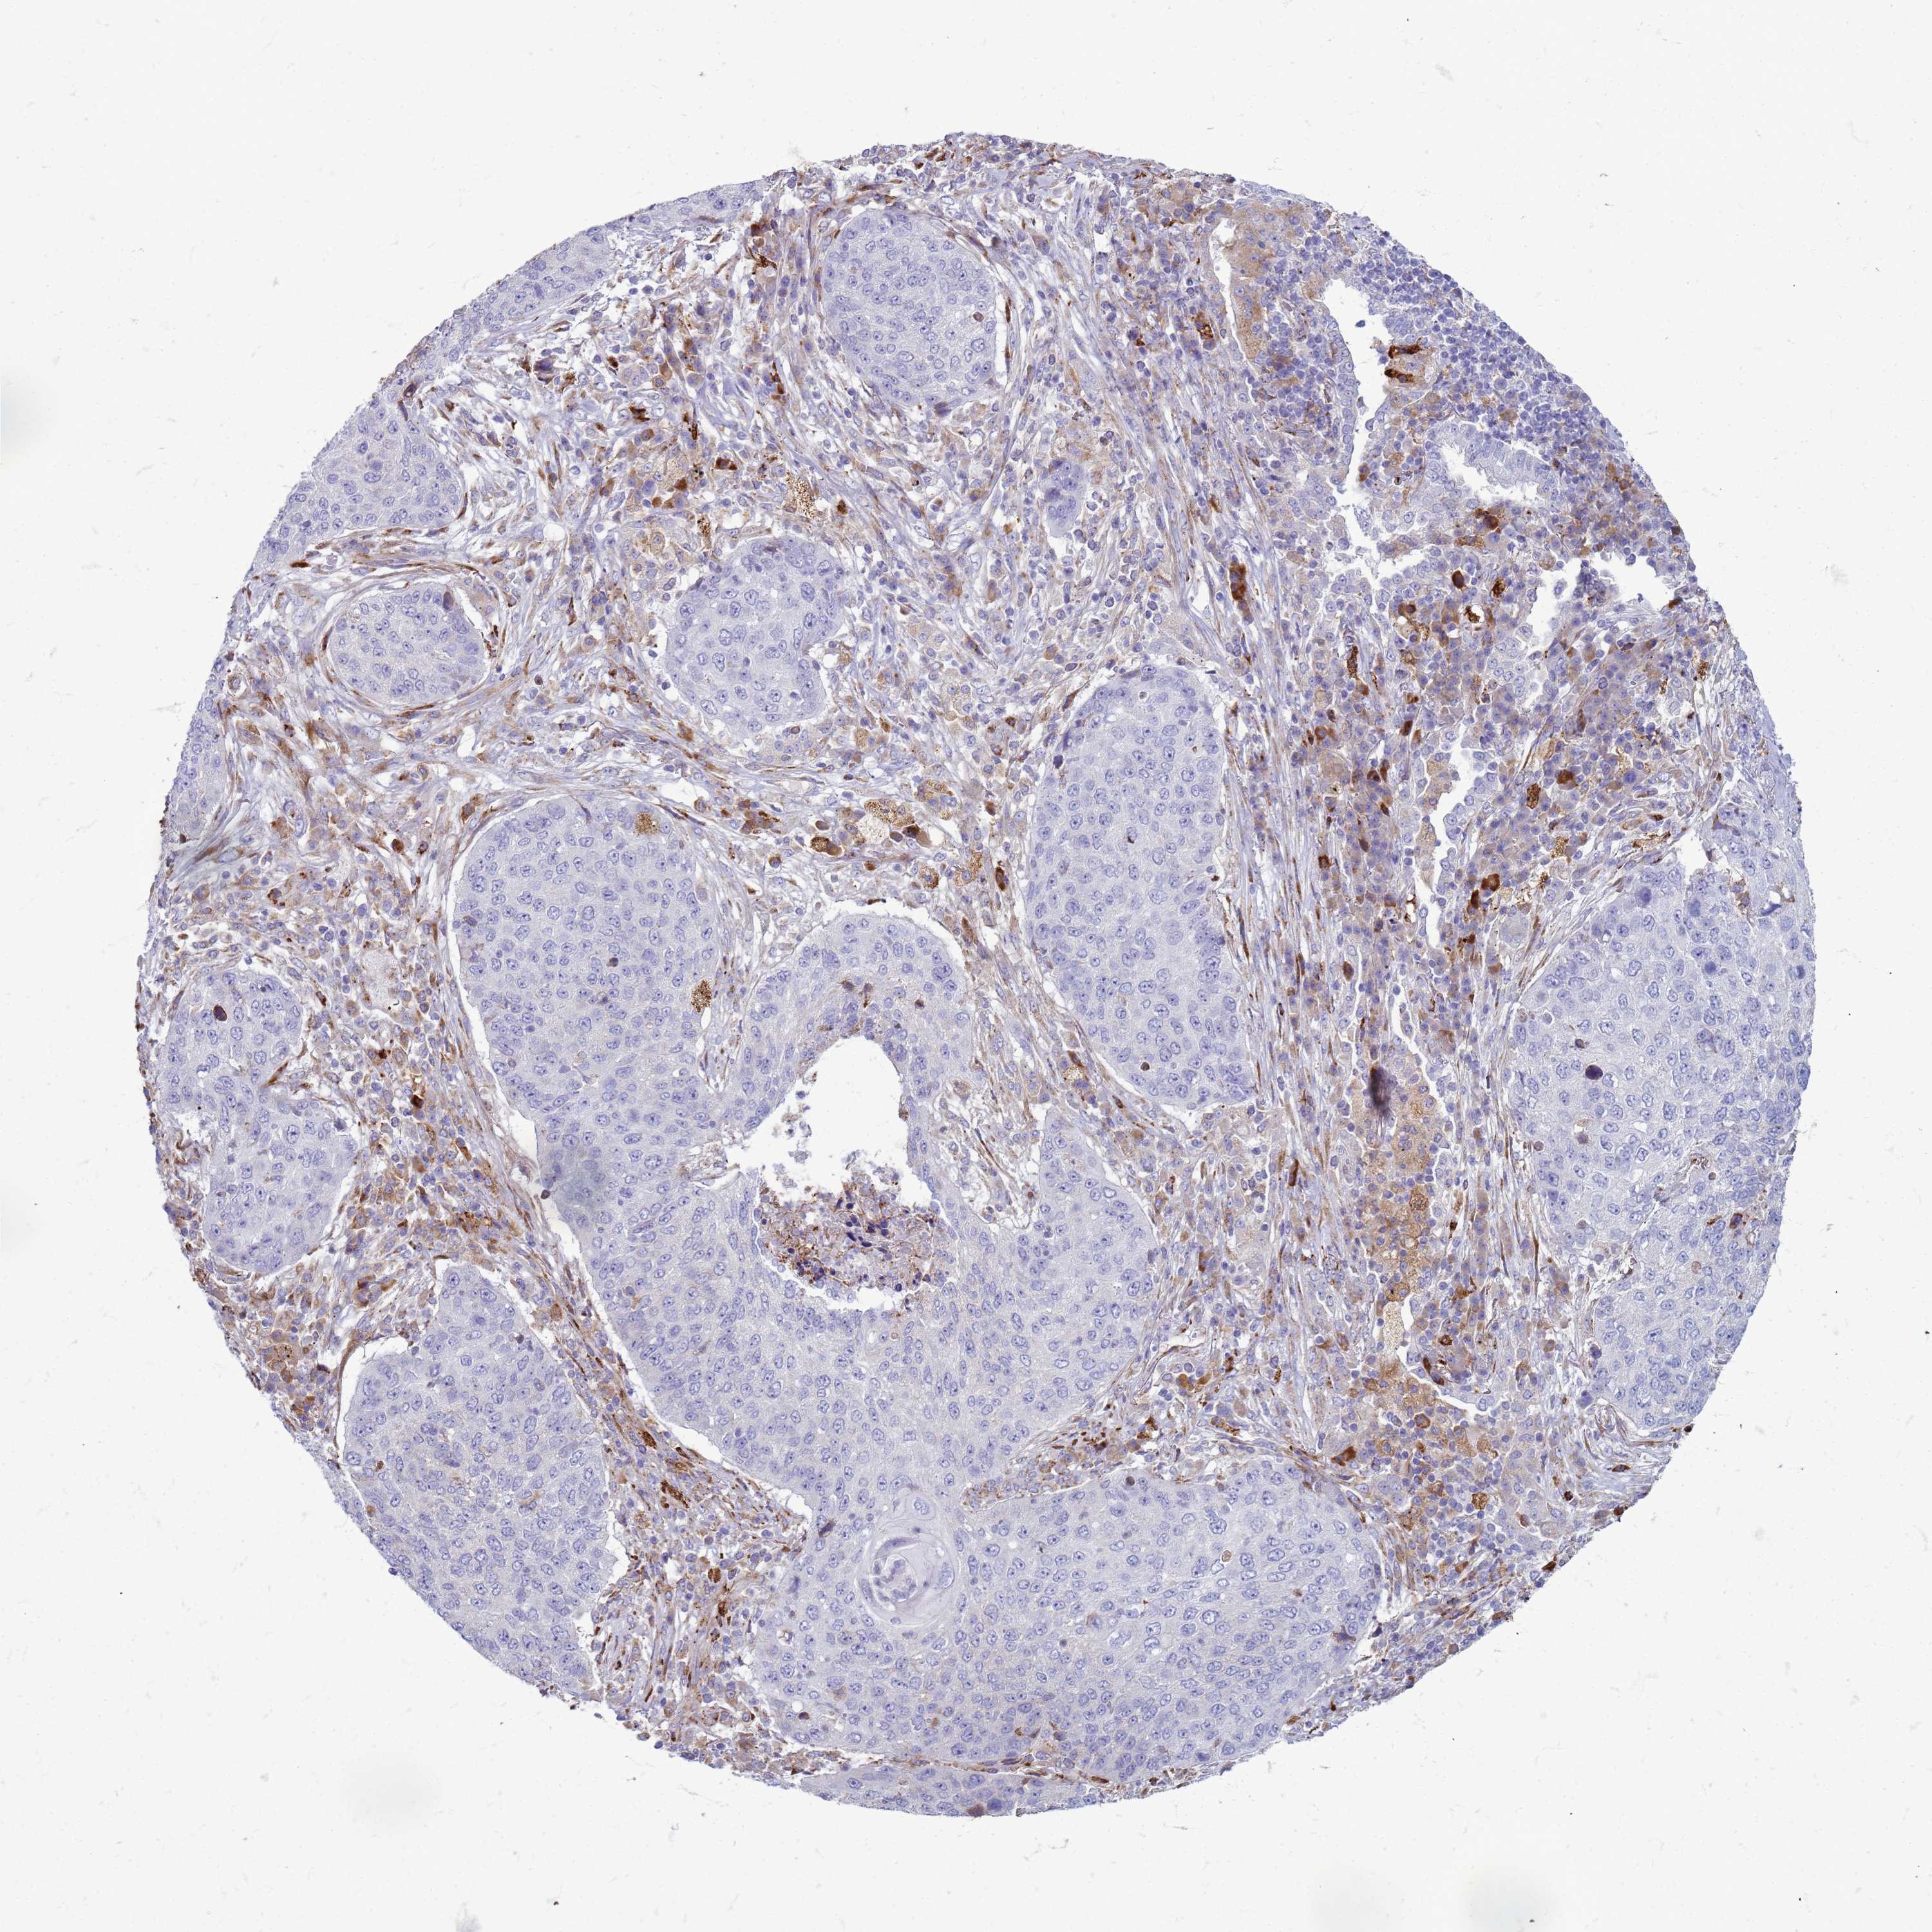

LUNG SQUAMOUS CELL CARCINOMA (TCGA) - Interactive survival scatter ploti

The Survival Scatter plot shows the clinical status (i.e. dead or alive) for all individuals in the patient cohort, based on the same data that underlies the corresponding Kaplan-Meier plots. Patients that are alive at last time for follow-up are shown in blue and patients who have died during the study are shown in red.

The x-axis shows the expression levels (FPKM) of the investigated gene in the tumor tissue at the time of diagnosis. The y-axis shows the follow-up time after diagnosis (years). Both axes are complimented with kernel density curves demonstrating the data density over the axes. The top density plot shows the expression levels (FPKM) distribution among dead (red) and alive patients (blue). The right density plot shows the data density of the survived years of dead patients with high and low expression levels respectively, stratified using the cutoff indicated by the vertical dashed line through the Survival Scatter plot. This cutoff is automatically defined based on the FPKM cutoff that minimizes the p-score. The cutoff can be changed by dragging the vertical line or by entering a cutoff value in the square labeled "Current cut-off".

Under the Survival Scatter plot the p-score landscape (black curve; left axis) is shown together with dead median separation (red curve; right axis). Dead median separation is the difference in median mRNA expression between patients who have died with high and low expression, respectively. It is calculated as follows: median FPKM expression of dead patients with high expression - median FPKM expression of dead patients with low expression. This is intended to aid the user in visually exploring custom cutoffs and the associated p-scores and dead median separation.

Individual patient data is displayed and can be filtered by clicking on one or more of the category buttons on the top of the page. Categories describing expression level and patient information include: high, low, alive, dead, female, male and tumor stages. The scale of the x-axis can be toggled between linear and log-scale by clicking on the "x log" button. Mouse-over function shows TCGA ID, patient information and mRNA expression (FPKM) for each patient.

& Survival analysisi

Kaplan-Meier plots summarize results from analysis of correlation between mRNA expression level and patient survival. Patients were divided based on level of expression into one of the two groups "low" (under cut off) or "high" (over cut off). X-axis shows time for survival (years) and y-axis shows the probability of survival, where 1.0 corresponds to 100 percent.

PDK3 is not prognostic in Lung Squamous Cell Carcinoma (TCGA)

Best expression cut offi

Based on the FPKM value of each gene, patients were classified into two groups and association between prognosis (survival) and gene expression (FPKM) was examined. The best expression cut-off refers the FPKM value that yields maximal difference with regard to survival between the two groups at the lowest log-rank P-value. Best expression cut-off was selected based on survival analysis .

When clicking on this number, the vertical dashed line indicating cut-off, the interactive survival plot, and the Kaplan-Meier curve will be adjusted to show results based on the best expression cut-off.

: 6.59

P scorei

Log-rank P value for Kaplan-Meier plot showing results from analysis of correlation between mRNA expression level and patient survival.

N/A

5-year survival highi

5-year survival for patients with higher expression than the expression cutoff.

For melanoma and glioma, 3-year survival is shown.

5-year survival lowi

5-year survival for patients with lower expression than the expression cutoff.

TCGA RNA samplesi

RNA-seq data is reported as average FPKM (number Fragments Per Kilobase of exon per Million reads), generated by the The Cancer Genome Atlas (TCGA) .

Normal distribution across the dataset is visualized with box plots, shown as median and 25th and 75th percentiles. Points are displayed as outliers if they are above or below 1.5 times the interquartile range. FPKM values of the individual samples are presented next to the box plot.

Average pTPM 8.0

Number of samples 489